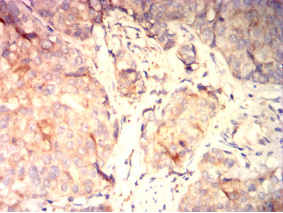

IHC    1/200-1/1000